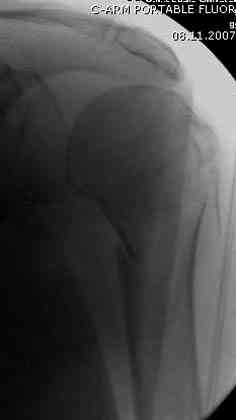

[Ortho] Оскольчатый перелом шейки, головки плечевой кости

Имя     : 1 Proximal humerus injury.jpg

Url     : http://weborto.net:8080/pipermail/ortho/attachments/20071128/ffd31465/attachment-0006.jpg